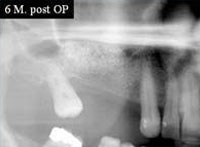

Die Folgen eines Zahnverlusts führen neben der reduzierten Kaufunktion und Ästhetik vor allem zu einem Knochenverlust. Die Ursachen sind in der fehlenden bzw. unphysiologischen Kaukrafteinwirkung. In extremen Fällen kann der Kiefer so weit schrumpfen, dass ein Prothesenhalt nicht mehr möglich ist, und sogar der Kiefer bei extremen Fällen brechen kann.

Mit Hilfe von Knochenersatzmaterialien ist es möglich, den Kieferaufbau nach Zahnentfernung zu unterstützen, bzw. den Knochenabbau aufzuhalten. Allerdings stoßen diese Techniken dann auf Grenzen, wenn eine absolute Kieferkammerhöhung angestrebt wird. In solchen Fällen kommen vor allem körpereigene Transplantate in Betracht.